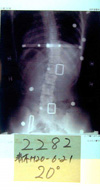

(3)次に大塚整体指導装具での腰椎湾曲女子の改善症例を見てみましょう。

写真(b)から見てもわかりますように、左腰椎湾曲タイプの体型です。

写真(a)(b)と比較しても体型が似ているが写真(a)の方が湾曲度が高いでしょう。

(b)初診29度 |

→ |

(c)改善中15度 |

H18/8/20 |

|

H19/9/5

●大塚整体では側湾症の要因を発見、このポイントで装具を作成、補強することにより格段に改善される。 米国はまだ知らない。そのため米国からも多くの方が来院されることは周知の事実。